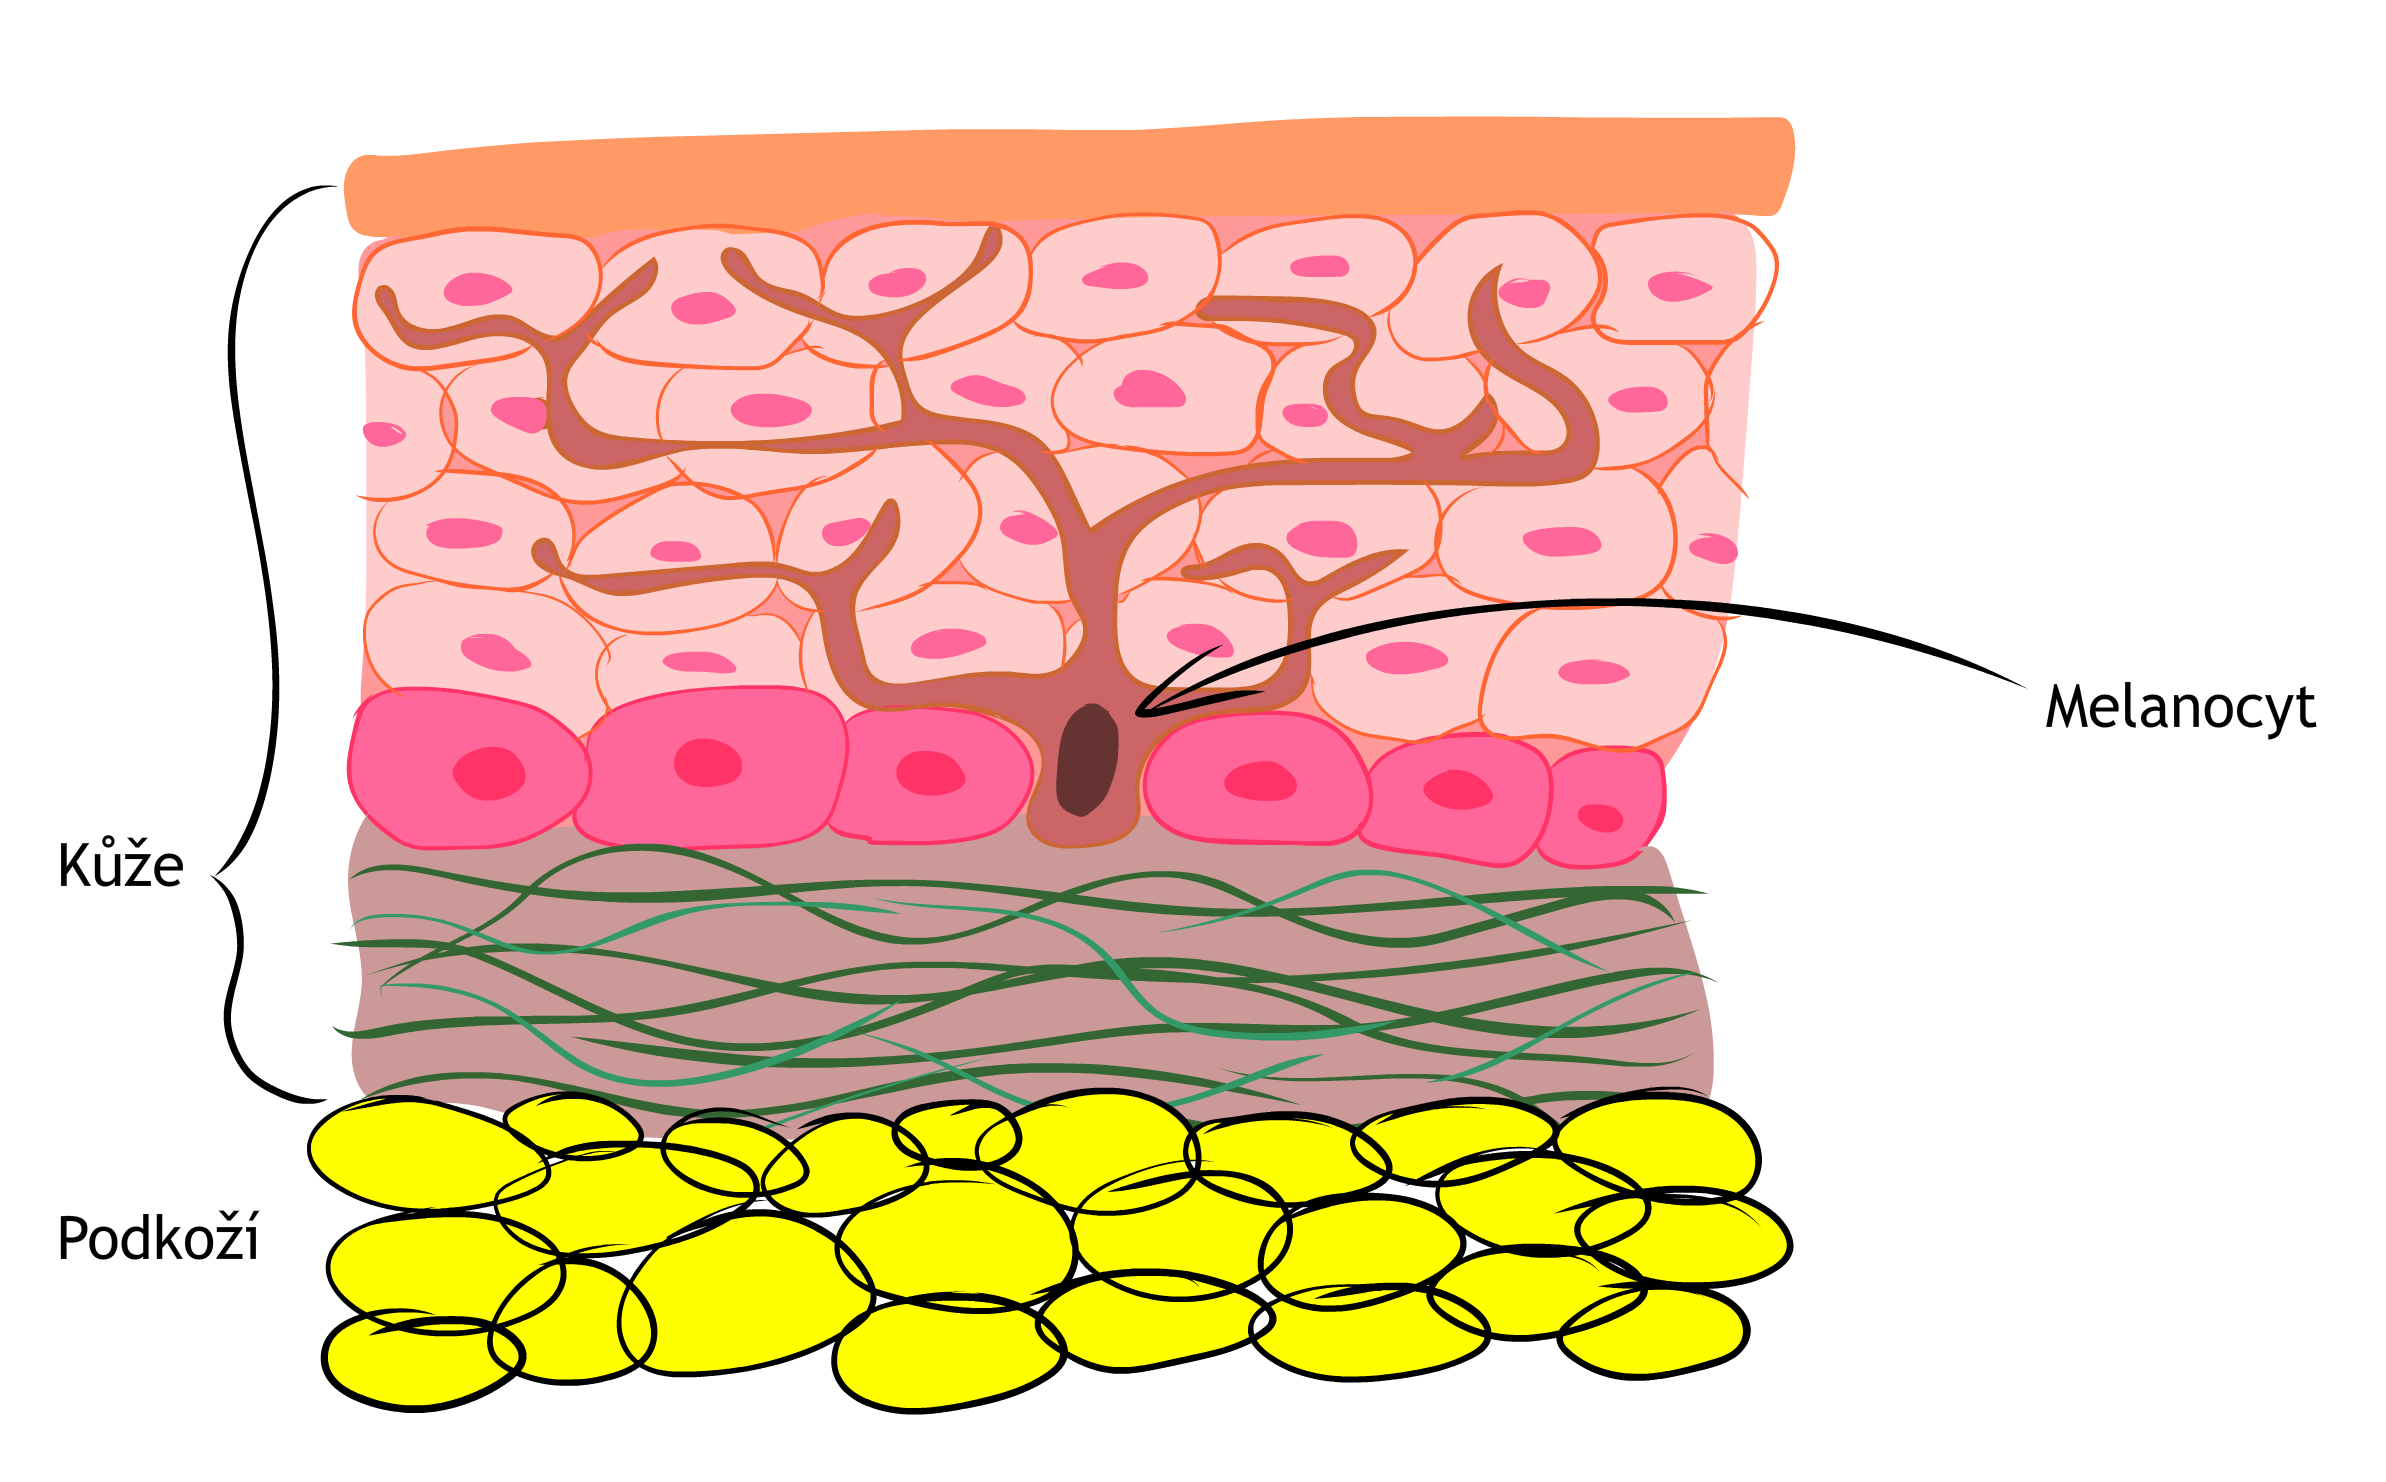

Maligní melanom je vážné onemocnění kůže, které vzniká z buněk zodpovědných za tvorbu pigmentu (barvy) kůže – tzv. melanocytů. Největším rizikem pro vznik melanomu je sluneční záření, zejména UVB paprsky. Lidé se světlou pletí, pihami a světlými vlasy jsou více náchylní k poškození kůže, a tím i ke vzniku melanomu. Dalším faktorem je dědičnost. U některých lidí se melanom vyskytuje častěji kvůli genetickým změnám, které se v rodině předávají. Tyto změny mohou zvyšovat riziko, že buňky v kůži začnou nekontrolovaně růst a vytvoří nádor.